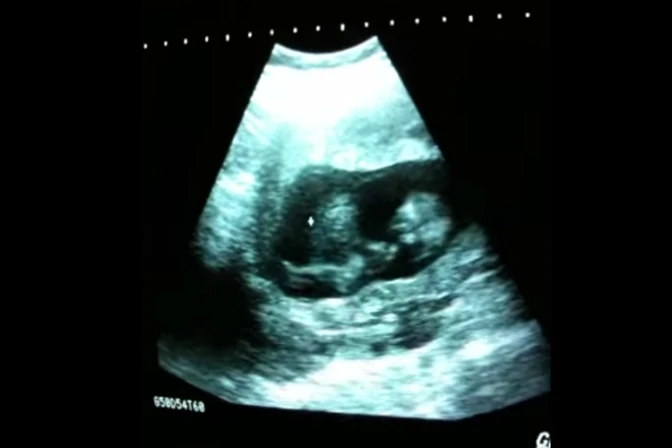

Una bebé de entre 8 y 12 semanas juega dentro del vientre de su madre en un video que ha superado las 3 millones de reproducciones en YouTube.

En el video, que corresponde a una ecografía de rutina, se puede observar a la bebé tomando repetidamente impulso a manera de columpio, dentro del útero de su madre.

Sherine Gayle-Slater, la madre de la bebé, recordó que este corresponde a una ecografía tomada "en algún momento entre las 8 y 12 semanas de embarazo, porque no podía sentir sus movimientos".